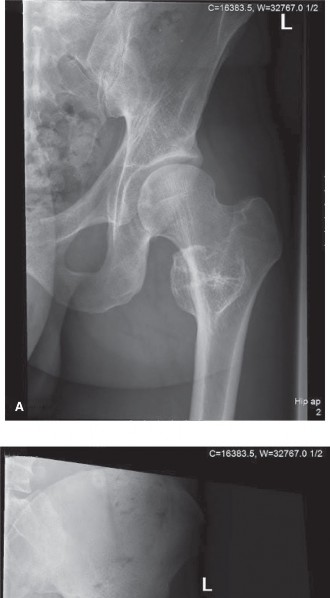

A 34-year-old man presents to your office complaining of increasing pain in his hip and thigh. He reports tha…